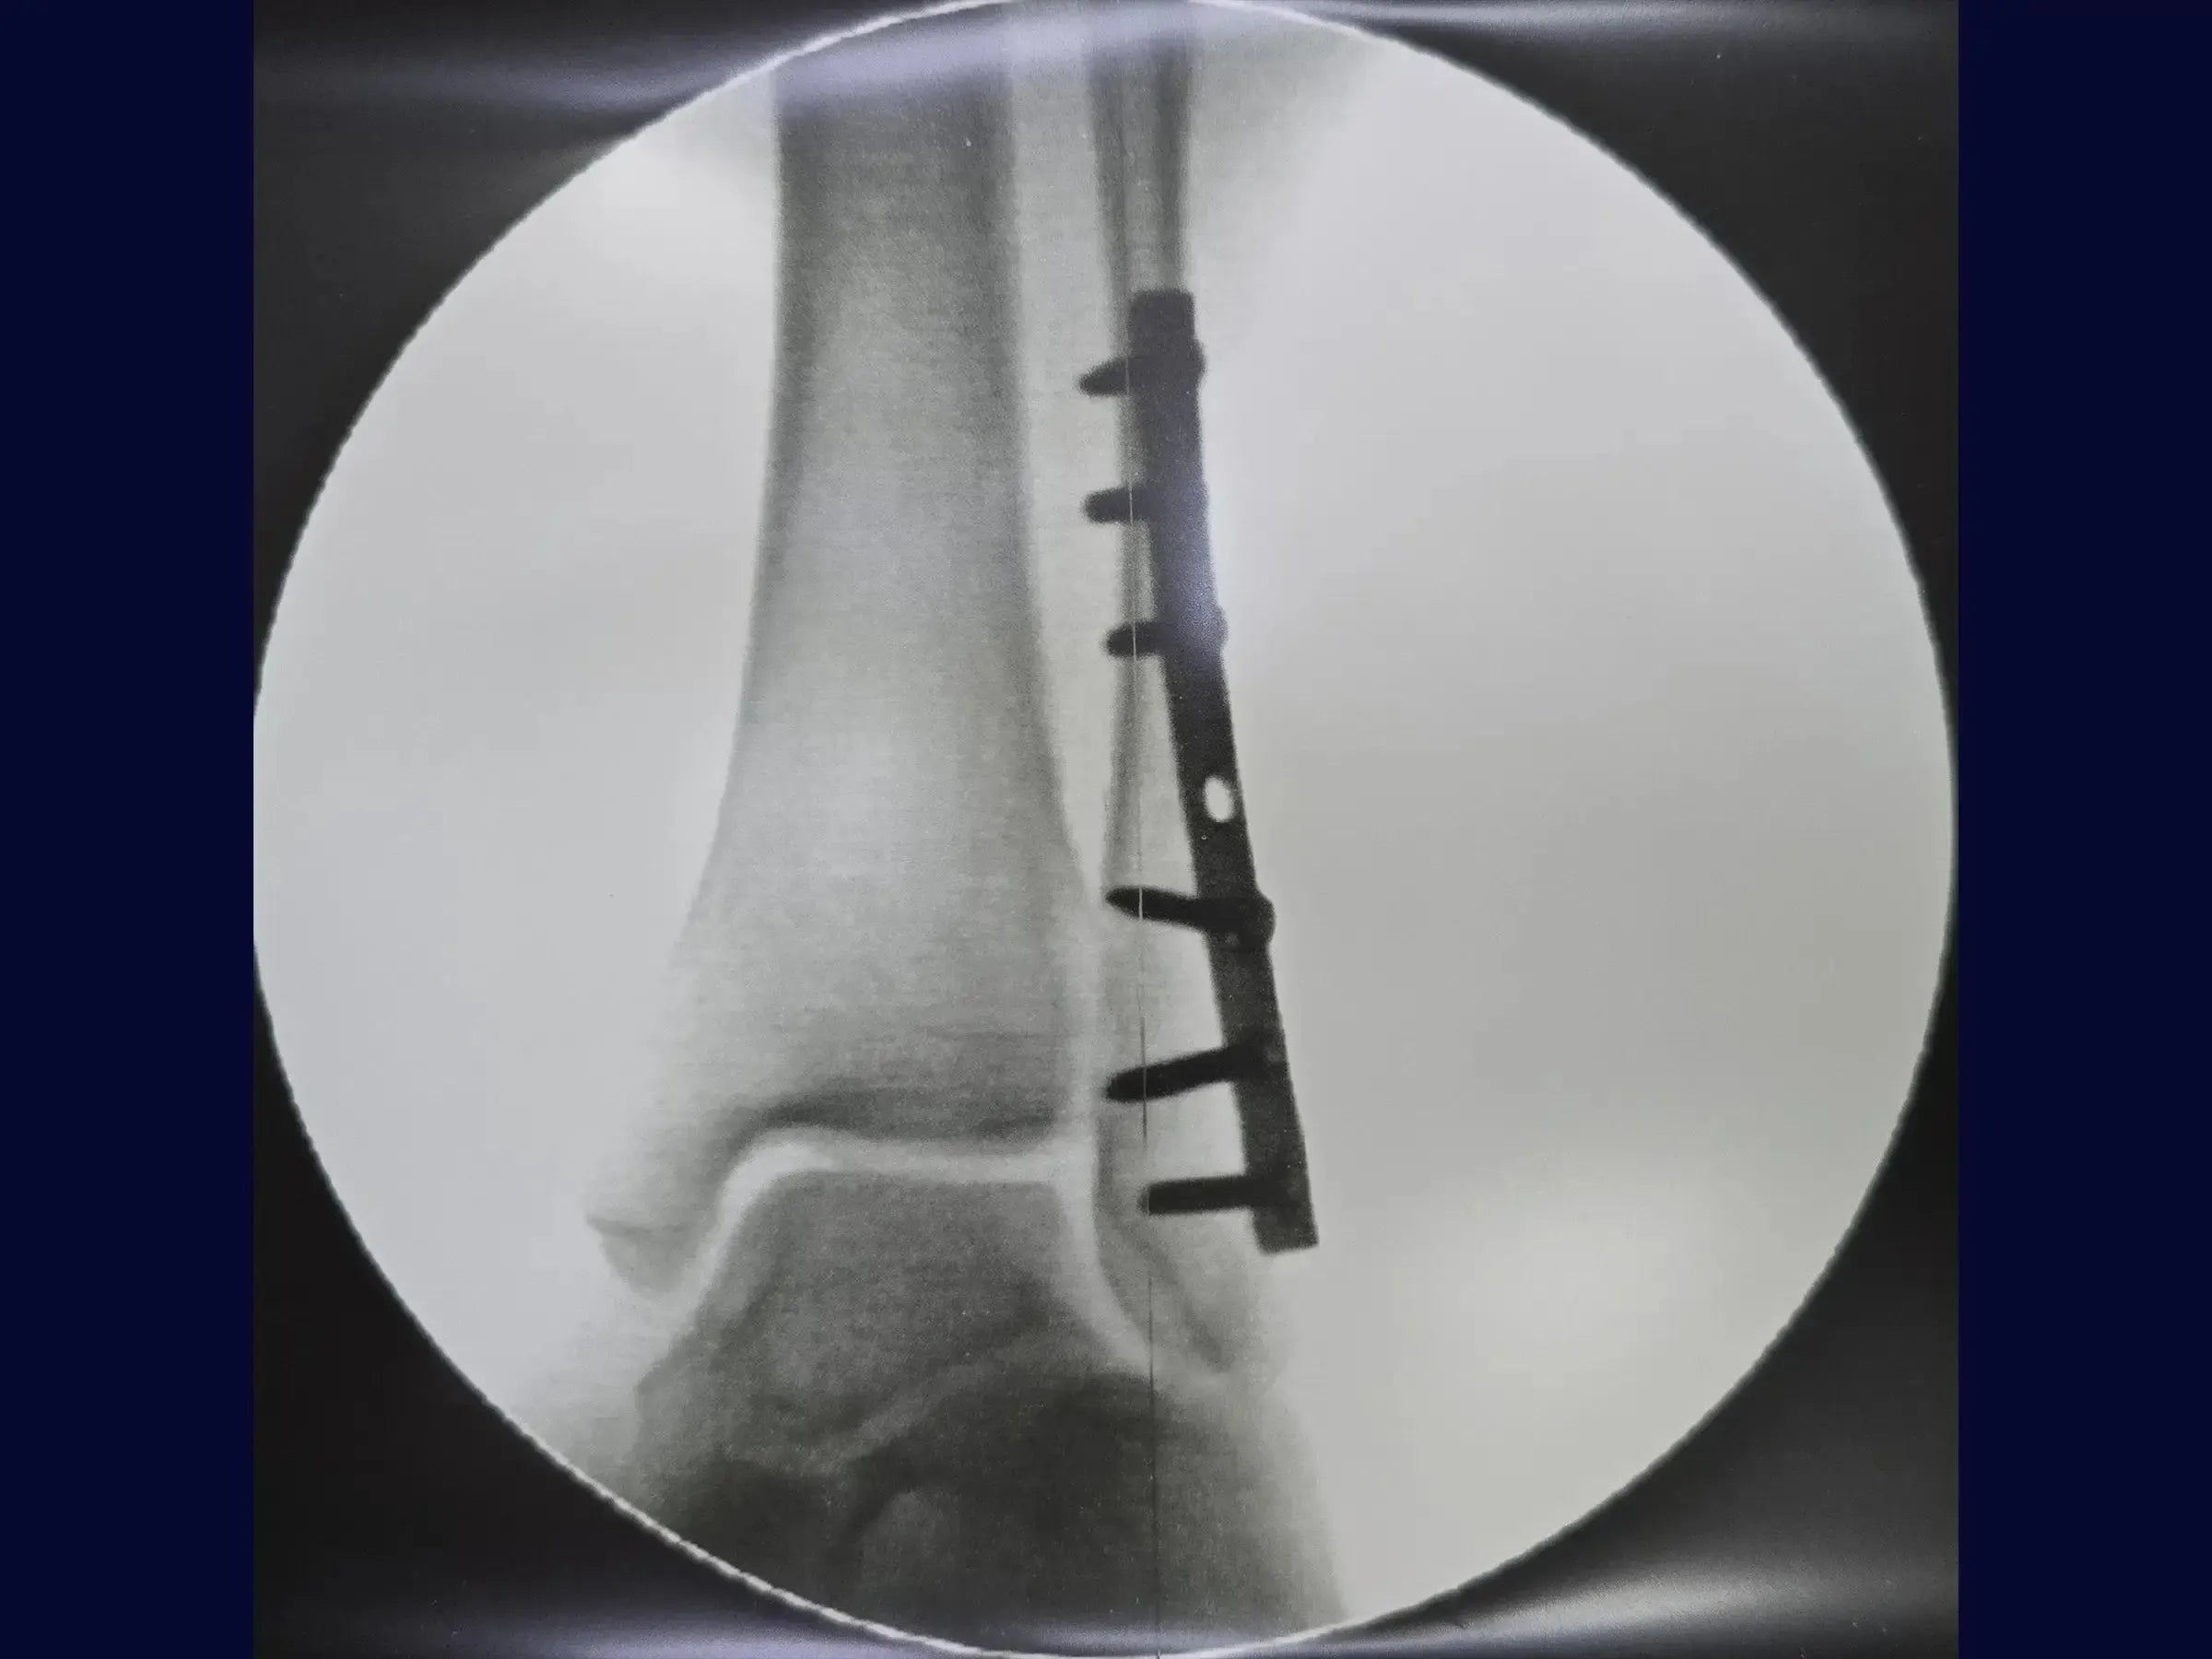

- Técnica de osteossíntese com placa posterior para controle do cisalhamento.

- Estratégia Adaptativa com Placa Posterior: Abordagem para gerenciar fraturas complexas e fragmentadas, garantindo estabilidade e redução.

- Fixação com Parafuso de Tração da Placa: Posicionamento estratégico do parafuso para estabilização da fratura através da compressão.

- Modelagem Distal da Placa: Prevenção de irritação de tendões fibulares, otimizando o conforto pós-operatório.

- Visualização Detalhada em 4K (Perspectiva Cirúrgica): Análise de alta resolução dos passos cirúrgicos com detalhes anatômicos e instrumentais.

- Análise Pós-Procedimento de Decisões Intraoperatórias: Compreensão crítica das escolhas cirúrgicas e seus fundamentos.